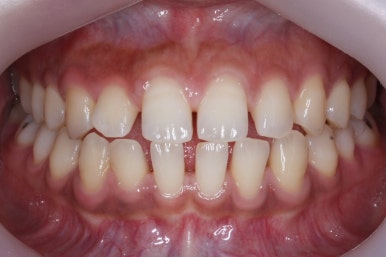

위 사진은 부산치아교정치과에 내원하셨을 대 당시의 입안 모습입니다.

치아들 사이에 전반적으로 틈이 많이 있는 상태입니다.

전반적으로 흩어져 있던 틈새를 특정 위치로 모으기 시작합니다.

앞니 사이의 틈을 제일 보기 싫어하실 것 같으므로 앞니 부터 빠르게 틈을 보아줍니다. 대신 작은 어금니 부위로 틈을 모으는 작업을 하게 됩니다.

점점 앞니 사이의 틈이 없어지는 것을 볼 수 있습니다.

앞니 사이의 없어진 틈은 대신 작은 억므니 부위로 모여져 갑니다.

앞니 사이의 틈이 이제 다 모아졌습니다.